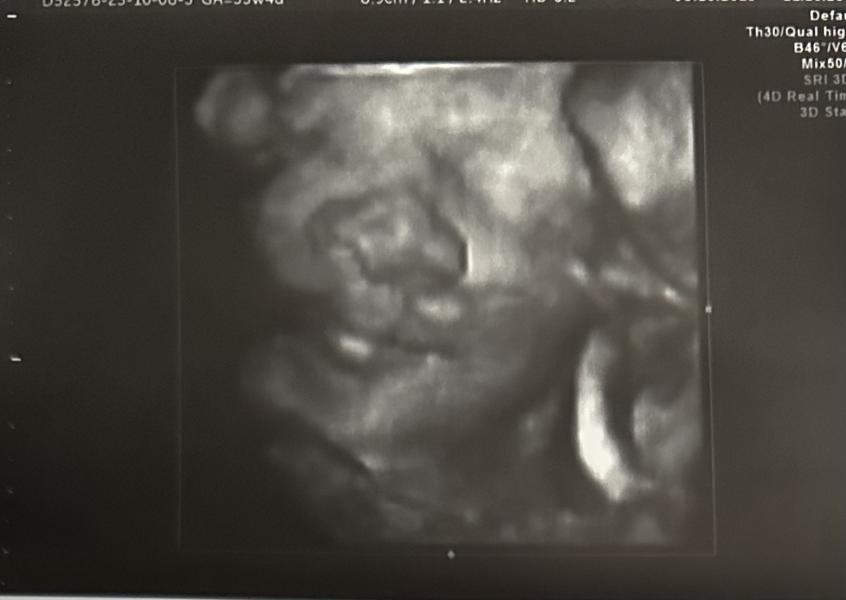

Третий скрин: эмоции счастья и ожидание нашего сладкого мальчика! Скорее бы увидеть улыбку!

Ходили на третий скрин, получили невероятные эмоции счастья, наш сладкий мальчик нам улыбался. Как же мы тебя ждем, наше большое счастье💕💕💕💕💕

Кажется ваши черты лица ☺️

Да, говорят, носик мой, а губки папины 🥰🤍